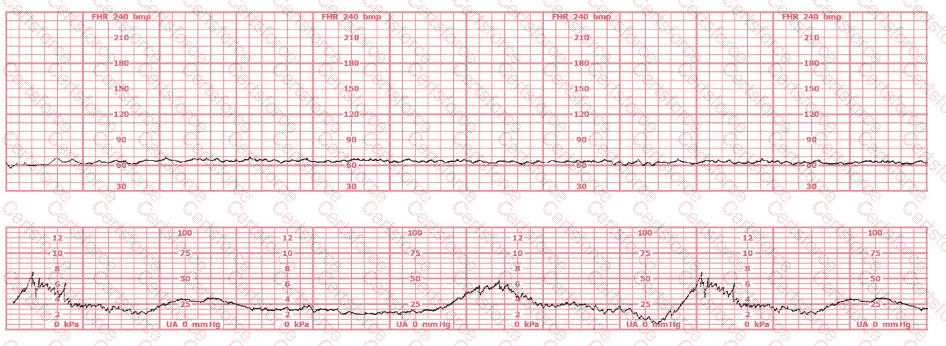

This fetal heart rate tracing is of a woman in labor with dichorionic-diamniotic twins at 36-weeks gestation, 4 cm dilated. She is on oxygen via face mask. Based on the fetal heart rate tracing, what is the most appropriate action?

(Tracing A = black; Tracing B = blue)